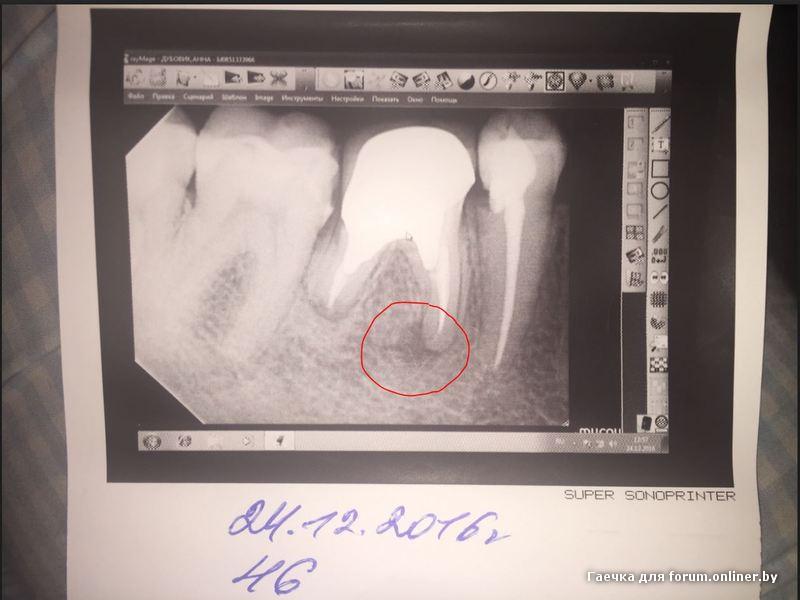

Здравствуйте! 4 дня назад заболел мертвый зуб под коронкой. Очень больно на него кусать в передней части (ближе к пятерке). Пошла к хирургу, сделала снимок. На корне образование. Решили, что удалить всегда можно и мне выписали Доксициклин и солевые полоскания. К сожалению, это совсем не помогло, всё равно болит, кусать невозможно и спать невозможно. Записалась на вторник на удаление. Зуб 46. У меня такой вопрос: если я его удалю, то как скоро можно будет поставить имплант? Сразу или ждать какое-то время. Хотелось бы сразу, но хирург у которой я буду удалять зуб имплантами не занимается. Можно ли удалить у нее (очень хороший специалист, вся моя семья ходит к ней), а потом идти к другому врачу на установку импланта в ближайшее время? Заранее спасибо за ответ.

P.S. на всякий случай фото

Гаечка:

Через 3-4 месяца.

А что лечить 5ку не сказала?